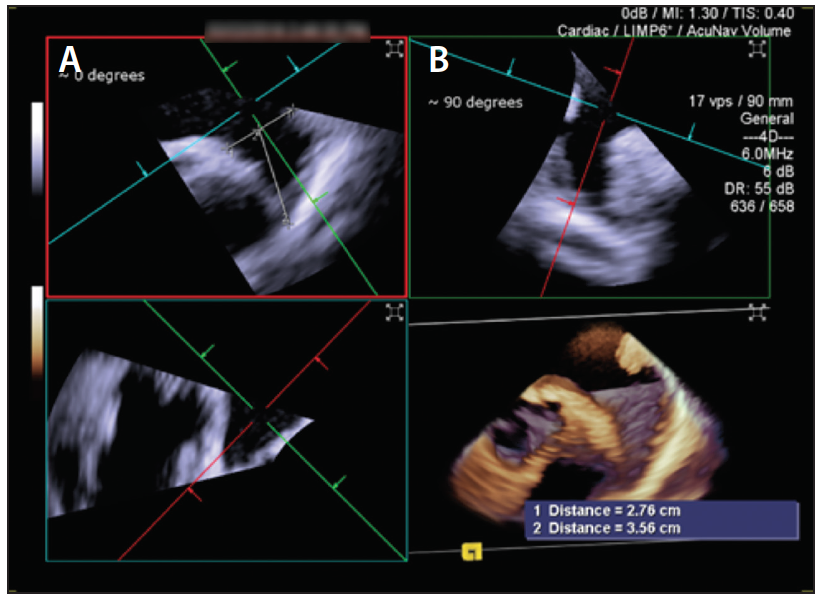

One of the concerns with such manipulations of the ICE probe in the left atrium is the risk of inadvertent injury, particularly in the thin-walled left upper pulmonary vein. Hence, a more recent advance is the utilization of 3D ICE, which obtains not only 3D reconstructed imaging (Figure 4 and Figure 5) but also, importantly, has the ability to do multiplanar reconstruction. All of these views by the 3D ICE probe can be achieved from a midleft atrial position, therefore obviating the need for aggressive probe manipulations in the left atrium and left pulmonary veins. A potential downside of the ICE probes remains their costs and impact on reimbursement.

Figure 5. By rotating the green plane 45° counterclockwise, we obtain the 0° and 90° views (A, B).